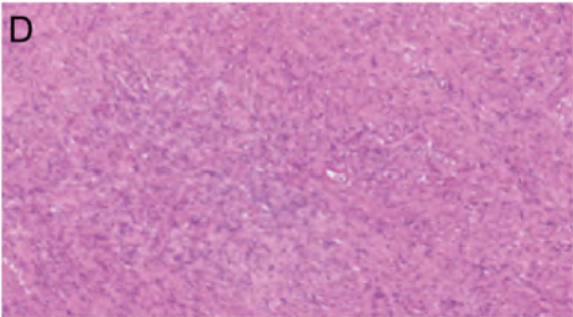

头颅MRI示:大脑镰走形区域、脑表面、双侧桥小脑角及双侧中颅窝颅底多发占位,伴双侧内听道累及、双侧海绵窦侵犯、上矢状窦侵犯(图1A)。颈椎MRI示:椎间隙未见明显变窄,脊神经增粗,椎管及双侧椎间孔见多发大小不等异常信号,T1呈等信号,T2呈高信号,信号欠均匀,较大者大小约为30mm×10mm,增强可见明显强化(图1B)。入院诊断为NF2。

术后转入神经外科重症监护室继续治疗,头颅CT未见术区明显出血,肿瘤切除满意(图1C)。肿瘤组织病理证实左侧延髓占位为神经鞘瘤,右侧延髓占位为脑膜瘤(图1D)。免疫组化示:CD34(血管+),结蛋白(desmin)(-),平滑肌肌动蛋白(SMA)(灶+),EMA(部分+),Ki-67(4%+),PR(部分+),GFAP(-),S-100(部分+)(图1E),CD56(部分+),WT1(-),促生长素抑制蛋白受体2(SSTR2)(部分+),信号转导和转录激活因子6(STAT6)(-)。

图1 患者术前及术后影像学、病理结果。A. 术前头颅 MRI 增强图像,可见双侧桥小脑角及双侧中后颅窝颅底明显强化,强化多均匀;B. 术前颈椎 MRI 增强图像,可见椎管及双侧椎间孔内多发大小不等异常信号,星明显强化,较大者大小约30 mm× 10mm;C. 术后头颅CT平扫

,术区无明显出血,肿瘤切除满意;D. 右侧延髓肿瘤组织病理结果(HE染色 x100);E. 延髓肿瘤组织S-100 免疫组化结果(x100)。